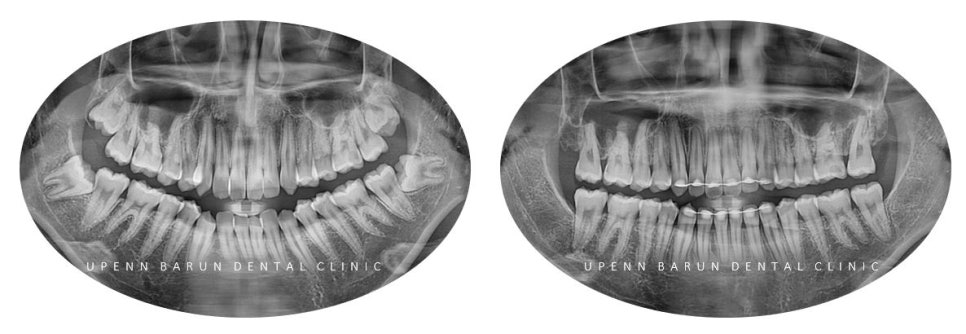

교정기간 21/6 ~ 24/2

위, 아래 앞니가 정확히 맞물리지 않았던 이전과는 달리

악궁확장기능이 있는 데이몬 교정을 통해 '발치를 하지 않고'

치아들이 제 자리를 찾으며

가지런히 펴졌는데요 ^^